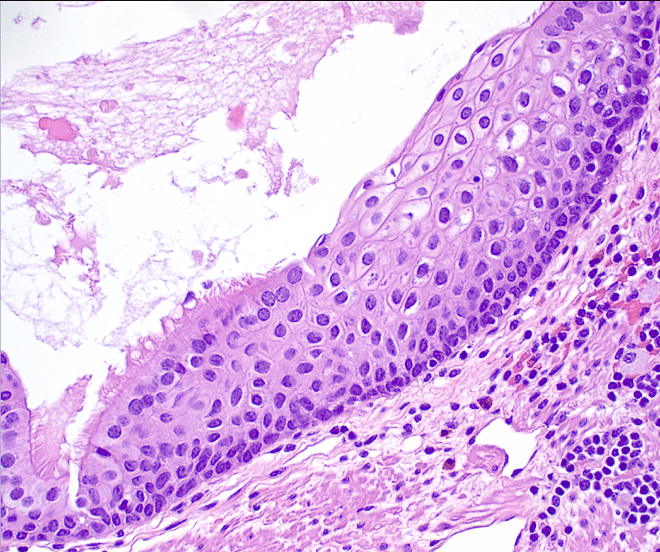

Microscopic findings

Cystic structure with a discrete muscular lining and an epithelial surface variably composed of nonkeratinizing squamous epithelium and ciliated, pseudostratified columnar epithelium with subepithelial seromucinous glands.

Figure 4. This area of the cyst lining shows a clear transition between the ciliated pseudostratified columnar epithelium and the stratified squamous mucosa (40x).